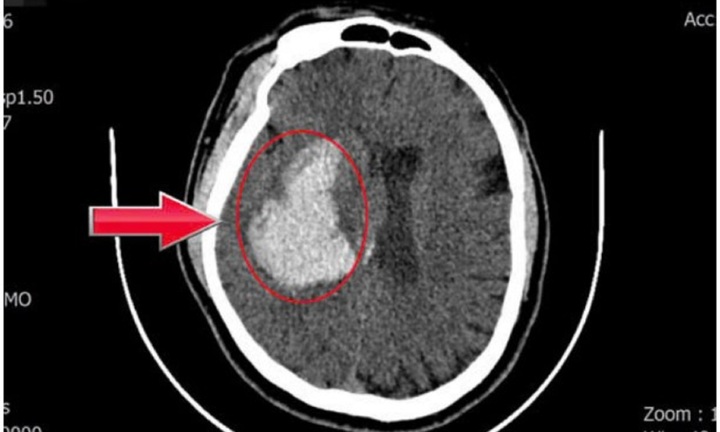

Theo Bệnh viện Nhân dân 115 (TP.HCM), đơn vị này vừa cứu sống thành công hai mẹ con du khách người Nga sau một tai nạn giao thông nghiêm trọng.